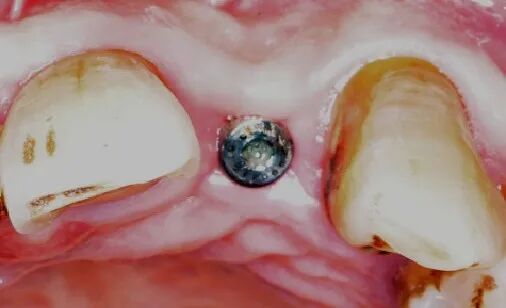

术后8周

牙龈软组织愈合,角化附着龈健康,口腔卫生一般,嘱患者重视日常口腔卫生维护。

术后4.5个月口内照片

术后4.5个月根尖片

ISQ动度值颊舌/近远中为70/73。